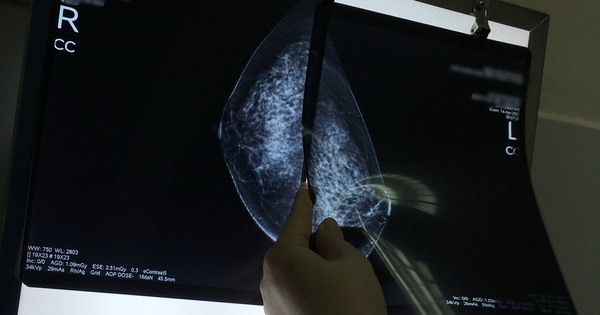

Bác sĩ đọc kết quả chụp nhũ ảnh của một bệnh nhân - Ảnh: MINH ANH

Trí tuệ nhân tạo (AI) có thể giảm gần 50% khối lượng công việc của các bác sĩ chẩn đoán hình ảnh trong tầm soát và phát hiện dấu hiệu ung thư vú, cũng như phát hiện ung thư chính xác hơn 20% so với phương pháp sàng lọc truyền thống.

Theo đó, nhóm nghiên cứu đã xem xét kết quả chụp X-quang vú của 80.000 phụ nữ ở 4 địa điểm miền Tây Nam nước này trong giai đoạn từ tháng 4-2021 đến tháng 7-2022. Phim X-quang tiếp đến được phân chia ngẫu nhiên cho một hệ thống do AI hỗ trợ, hoặc nhóm đối chứng gồm hai bác sĩ chẩn đoán hình ảnh để phân tích.

Kết quả cho thấy AI có khả năng phát hiện thêm 20% số ca ung thư, tương đương thêm một trường hợp cho mỗi nghìn phụ nữ được sàng lọc. Trong khi đó tỉ lệ dương tính giả của hai nhóm giống nhau, ở mức 1,5%.

Cạnh đó, AI giúp giảm tải 44% khối lượng công việc do chỉ yêu cầu một bác sĩ hỗ trợ chẩn đoán thay vì hai người.